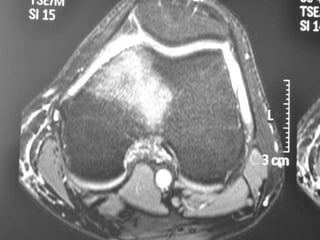

Osteoid Osteoma - MRI

• MRI has not been useful in the diagnosis of

osteoid osteoma.

• MRI is reserved for equivocal cases because it

can suggest the diagnosis of osteoid osteoma.

• MRI interpretation may result in errors in

diagnosis, most often confusion with

malignancies.

Osteoid Osteoma -MRI • MRI has not been useful in the diagnosis of osteoid osteoma. • MRI is reserved for equivocal cases because it can suggest the diagnosis of osteoid osteoma. • MRI interpretation may result in errors in diagnosis, most often confusion with malignancies.